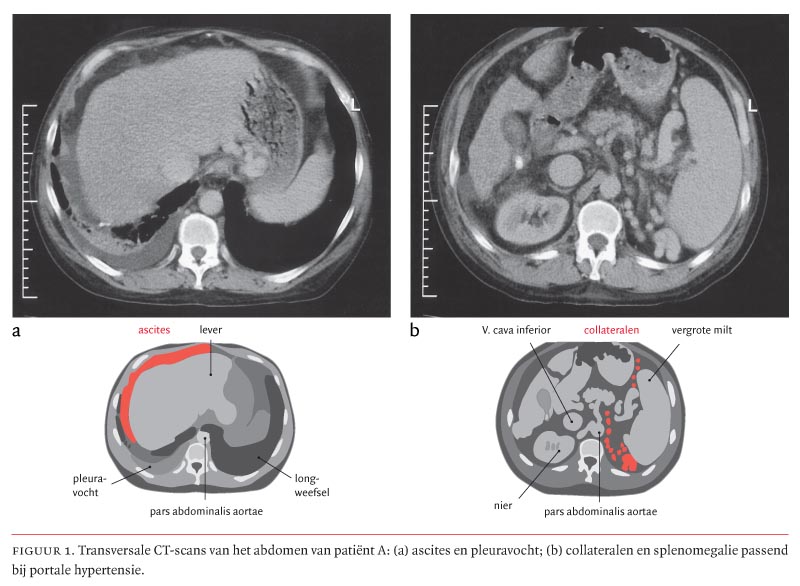

In het artikel van Kok et al. getiteld ‘Heterozygotie voor ?1-antitrypsinedeficiëntie als cofactor bij de ontwikkeling van een chronische leveraandoening’ (2005:2057-61) staan in figuur 1 enkele onjuistheden in de verklarende tekeningen bij de CT-opnamen. De juiste figuur gaat hierbij. Dr.ing.J.A.van Oostayen, afd. Radiologie, Ziekenhuis Rijnstate, Arnhem, droeg bij aan dit artikel.